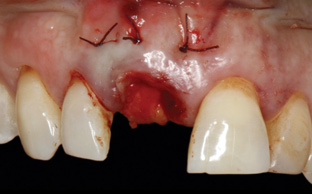

8. Tooth No. 8 with diagnosis of Grade III socket, requiring extraction followed by guided bone regeneration and a rotated pedicle flap to gain hard and soft tissue for future implant placement.

Figure 8

9. Tooth No. 8 with diagnosis of Grade III socket, requiring extraction followed by guided bone regeneration and a rotated pedicle flap to gain hard and soft tissue for future implant placement.

Figure 9

10. Tooth No. 8 with diagnosis of Grade III socket, requiring extraction followed by guided bone regeneration and a rotated pedicle flap to gain hard and soft tissue for future implant placement.

Figure 10

11. Tooth No. 8 with diagnosis of Grade III socket, requiring extraction followed by guided bone regeneration and a rotated pedicle flap to gain hard and soft tissue for future implant placement.

Figure 11

Based on the single extraction socket roadmap developed by El Chaar and colleagues, the socket of tooth No. 8 was diagnosed as Grade III and would require initial treatment that included the extraction of failing tooth No. 8 followed by simultaneous guided bone regeneration and soft-tissue augmentation by means of a rotated palatal pedicle flap (Figure 8 through Figure 11).27,28 The principles of and guidelines for both the ridge augmentation and rotated pedicle flap have been described in the literature and will not be focused on in this case report.27-30 The patient was temporized with a bonded Maryland bridge that was adjusted to avoid creating pressure on the tissue during healing (Figure 12).